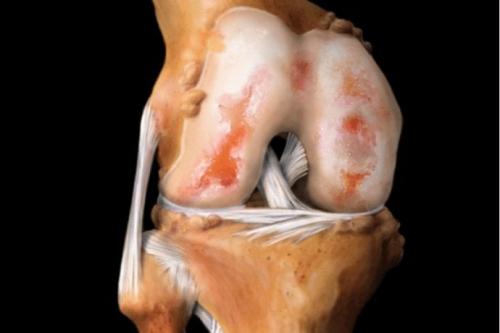

остеоартрит – болезнь, которая поражает в первую очередь хрящевую ткань суставов и кости, образующие сустав. хрящ, выстилающий сустав, изнашивается. организм стремится восстановить поврежденный хрящ, в результате чего вокруг сустава разрастается костная ткань. эти разрастания костной ткани раздражают и разрушают суставы, которые теряют свою естественную смазку, гибкость и издают характерный звук «хруста». для улучшения подвижности и скольжения суставов применяются препараты, направленные на молекулярно-структурное восстановление хрящевых сегментов.Долгое время мама пила, назначенный врачом препарат "Артра", эффекта от него особого не было, а входящий в состав глюкозамин гидрохлорид имел побочный эффект на жкт.

Удивительно, но хрящевая ткань коленного сустава устроена так, что ее очень легко можно повредить даже нагрузкой в 1 кг, приложенной не в том месте. Такое никогда не случится, если сустав заключен в прочный корсет связок, который удерживает кость в нужном положении.

Восстановление хряща коленного сустава возможно лишь при поступлении достаточного количества питательных веществ к хрящевой ткани. За день колени сгибаются и разгибаются огромное количество раз. Если существует недостаток смазки – синовиальной жидкости, то соприкасающиеся суставы будут все больше разрушать друг друга.

Кровь в коленный сустав практически не поступает (в суставных хрящах нет капилляров). При отсутствии должного питания рост и восстановление хрящевой ткани становятся невозможными. Для поддержки своего существования хрящевая ткань вынуждена брать нужные ей микроэлементы и витамины из синовиальной жидкости.